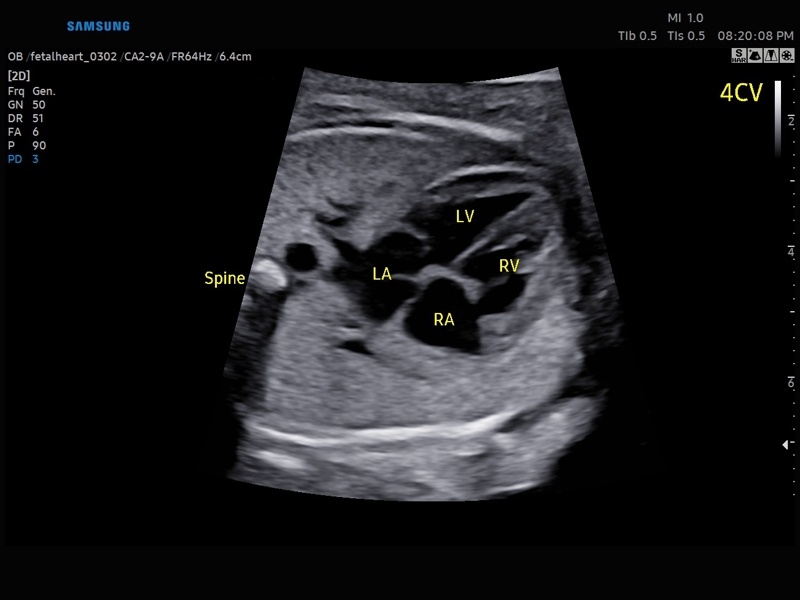

• Акушерство и гинекология

• Модуль5D HeartColor – программа автоматического построения основных срезов средца плода в режиме объемного сканирования с анализом кровотока.

• МодульSTIC- объемная динамическая визуализация сердца плода.

• Сердце плода:измерения в В-режиме (отношение площади сердца и грудной клетки), измерения в М-режиме (толщина межжелудочковой перегородки в диастолу, конечнодиастолический размер левого желудочка, толщина задней стенки левого желудочка в диастолу, толщина межжелудочковой перегородки в систолу, размер левого желудочка в систолу, толщина задней стенки левого желудочка в систолу, внутренний размер правого желудочка в диастолу), измерения в режиме спектрального допплера (легочный ствол, артериальный проток, нижняя полая вена, венозный проток, восходящая аорта, нисходящая аорта, трансмитральный кровоток, митральная регургитация, трикуспидальный кровоток, трикуспидальная регургитация, индекс преднагрузки, ЧСС).